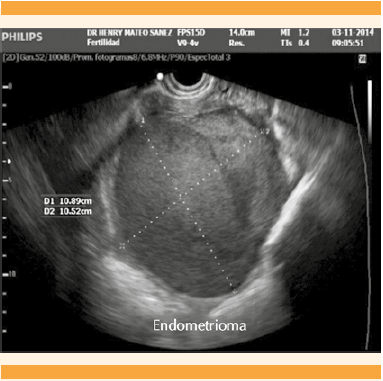

En la exploración física no se encontraron signos de fiebre ni datos de irritación peritoneal, pero percibió dolor moderado a la palpación en la fosa iliaca izquierda, que se irradiaba a la región lumbar y se extendía hasta el muslo posterior ipsilateral. En la evaluación física inicial se encontró útero en anteroversoflexión, cérvix central y posterior; a la palpación: fondo de saco posterior doloroso y ocupado por abultamiento de consistencia suave en más de 50% de la pelvis izquierda. El ultrasonido transvaginal del ovario izquierdo mostró una imagen compatible con endometrioma de 9.2 x 8.4 cm (Figuras 1 y 2).

Figura 1 Ultrasonido transvaginal (región adyacente al útero) que identifica el endometrioma de 10.8 x 10.5 cm, a expensas del ovario derecho.